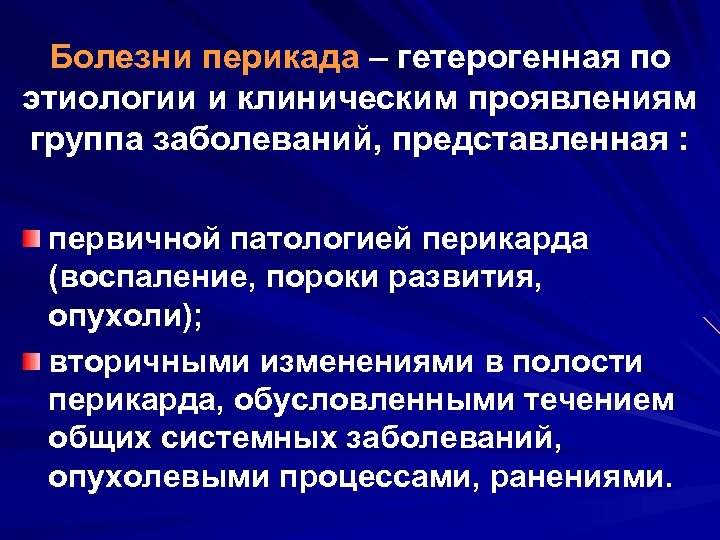

Болезни перикада – гетерогенная по этиологии и клиническим проявлениям группа заболеваний, представленная : первичной патологией перикарда (воспаление, пороки развития, опухоли); вторичными изменениями в полости перикарда, обусловленными течением общих системных заболеваний, опухолевыми процессами, ранениями.